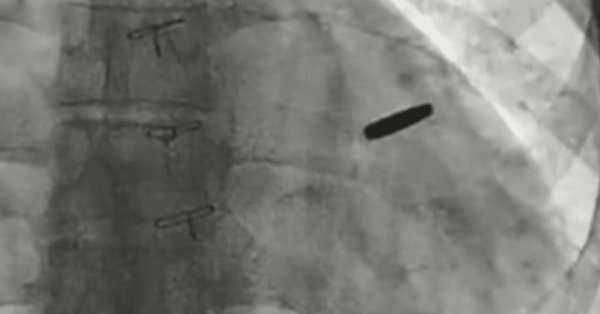

Украинские врачи взяли пулю, застрявшую в самом сердце солдата, который защищал сталелитейный завод Азовстала в Марипуле И он выжил в течение трех лет в российском плену, по словам Бориса Тодурова, директора Украинского института сердечных заболеваний, 19 сентября.

Тодуров сказал, что пуля чудесным образом пропустила жизненно важные структуры, которые Она позволила бойцам жить с ним, застряв в его сердце в течение трех лет.

«Пуля уже была взята. Человеку повезло. Я думаю, что он будет жить долгой и счастливой жизнью», — сказал Тодуров, держа пулю во время брифинга для прессы.

Врачи сказали, что пуля не нанесла серьезного ущерба в течение годов, когда он оставался застрявшим в сердце.

Украинский защитник провел три года в российском плену с пулей в своем сердце.

Украинский сердечный хирург Борис Тодуров сказал, что воин защищал Азовстала и после ранения был взят в плен в 2022 году. Его обменивались несколько месяцев назад.